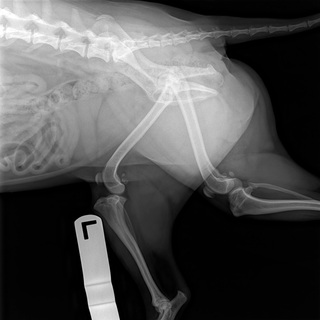

Positioning markers (right, left, front, hind) should be used so that the radiographs may be correctly interpreted. This is especially true for equine radiographs of areas distal to the carpus and tarsus or symmetrical anatomical areas such as a skull. Conventionally, markers are placed laterally (as opposed to medially) for DP, CrCd, or CdCr and oblique limb radiographs.

Place the markers cranially for lateral radiographs. In DV or VD views, place the appropriate L or R marker on the correct side of the patient. When a lateral projection of the body is taken, the marker should indicate the side that is directly on the table or cassette. Thus an R would indicate a patient lying in right lateral recumbency. The marker or label would generally be placed cranially and ventrally (Fig. 15.18).